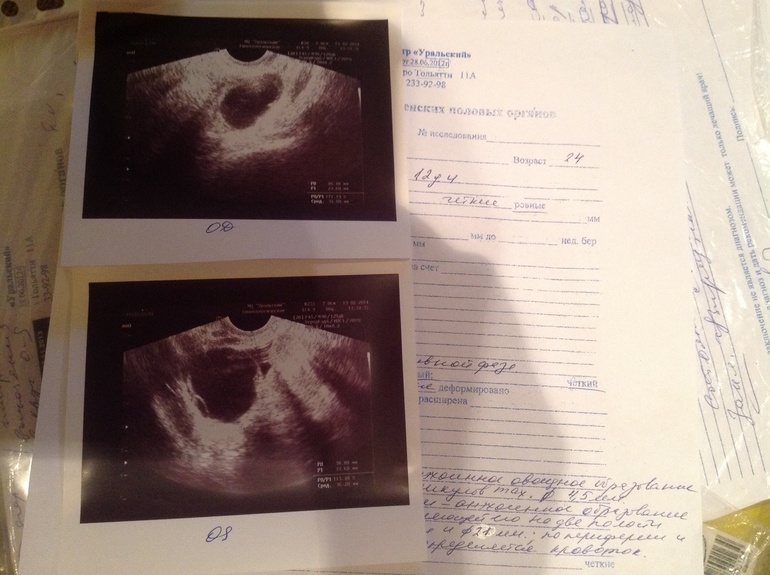

Фотки узи на 2 цикл отмены ок 12 день цикла